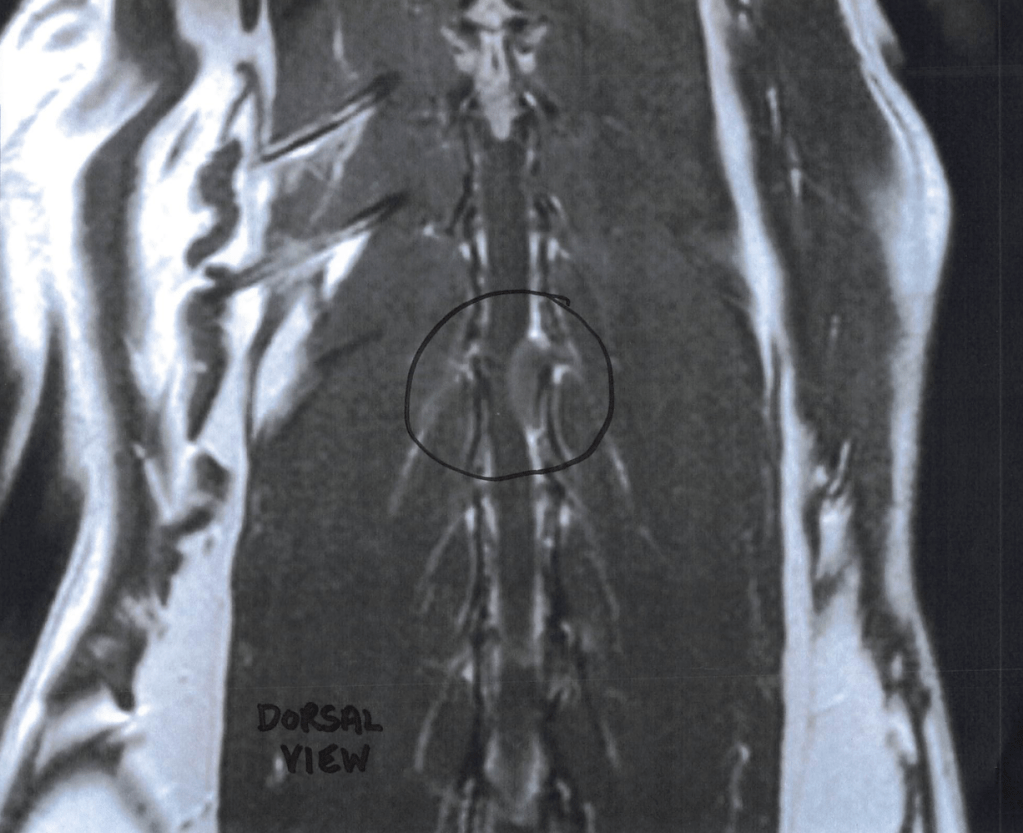

Three months after his initial limp tail diagnosis, Bradley began to regress. By the time he got an MRI, he started to lose strength in his back legs. MRI as a diagnostic test may be quite simple to administer to people, but for animals it requires a full sedation. I had to see what was going on. He deserved the best treatment I could afford.

The initial impression of his MRI results was devastating. Extradural mass compressing the spinal cord.

Without a biopsy it was impossible to determine the diagnosis. The radiologist and oncologist suggested “meningioma, lymphosarcoma, or other”. None of the options were good news. None of the suggestions would turn out to be correct.